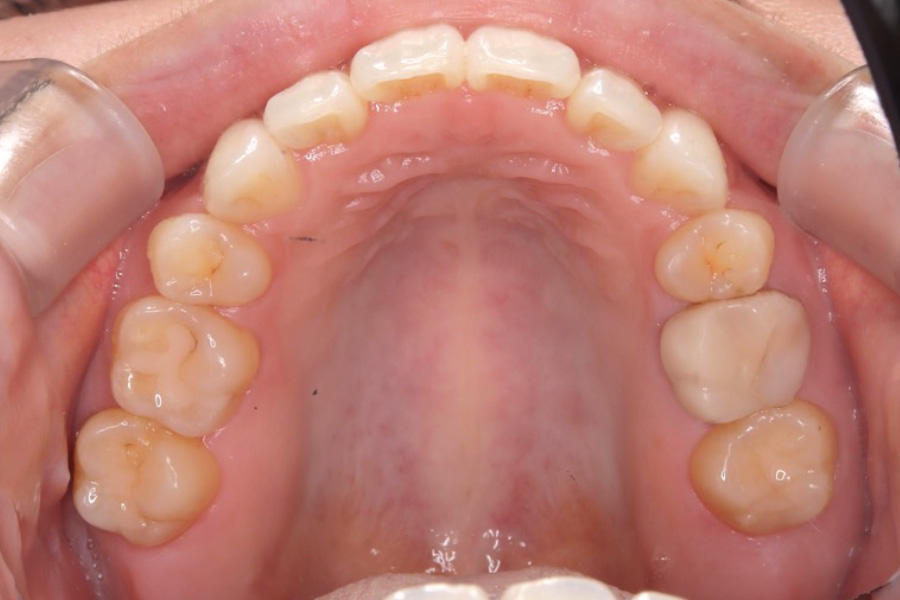

【20代女性】

歯のガタつき、突出感を

インビザライン矯正で治療したケース

治療後

主訴 歯のガタつき、突出感が気になる

治療内容 インビザライン矯正

小臼歯抜歯

治療に伴うリスク 矯正終了後は、リテーナーを指示通りに使用し、歯の後戻りを防ぐ必要があります。